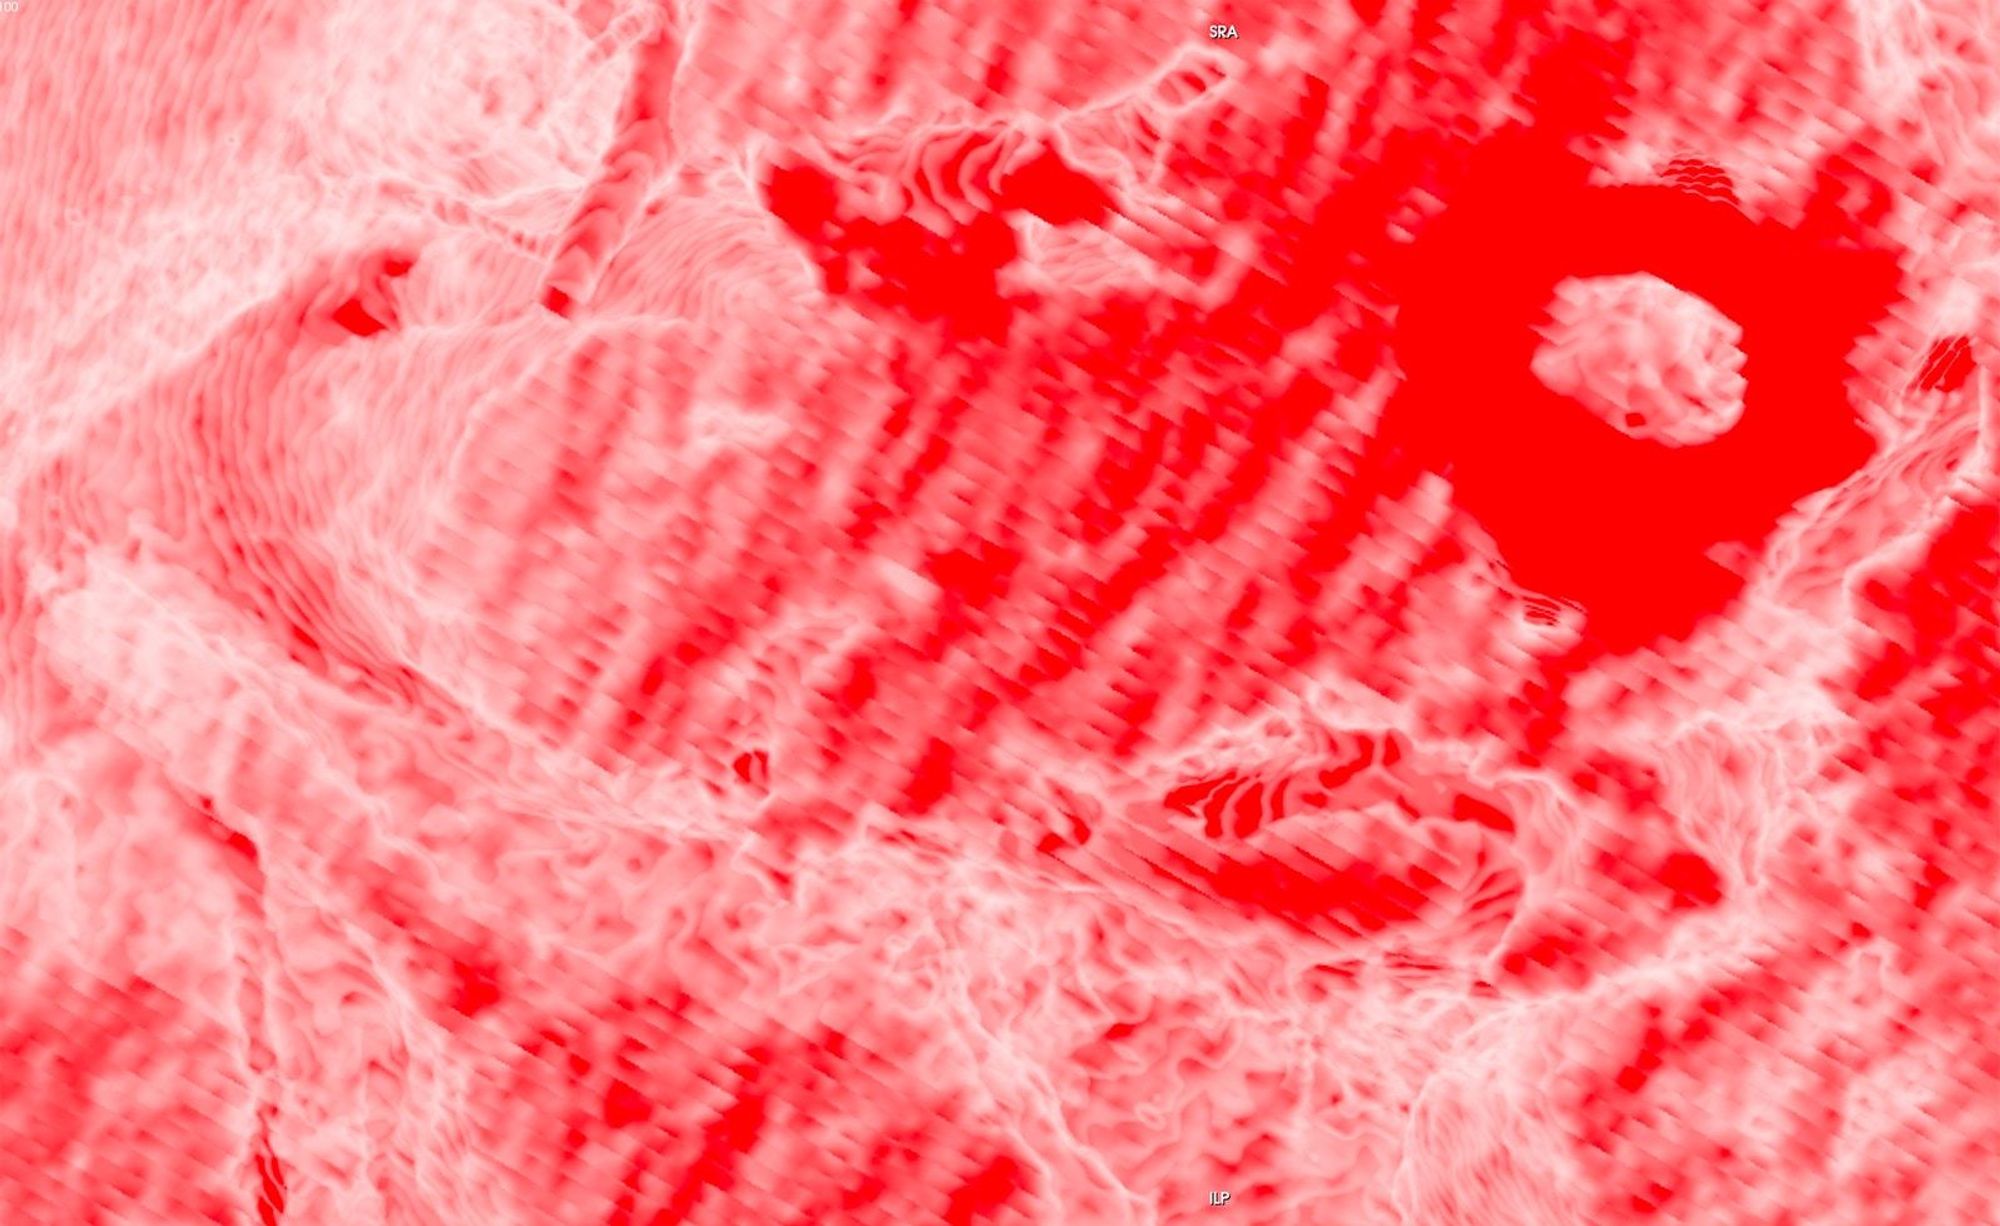

The history of medicine can be understood as an on-going endeavour to comprehensively visibilise the body, to pull it from obscurity, to open it out to vision. ‘The x-ray image, with its simultaneous view of the inside and outside, turned the vantage point of the spectator-subject inside out.’ * With the invention of the x-ray, the surface of the body, and its distinction from the world, was dissolved and lost in the image.

In this project, I look at the visual limit between the inside and the outside, the inner and the outer. I combine different visual approaches to materialise the body, using medical imagery, photography from manuals and radiology software. Decontextualised from their origin, these images speak of medicine’s relationship to both sex and violence, and remind us that, in medicine, to go into the body is always to go into the image first.